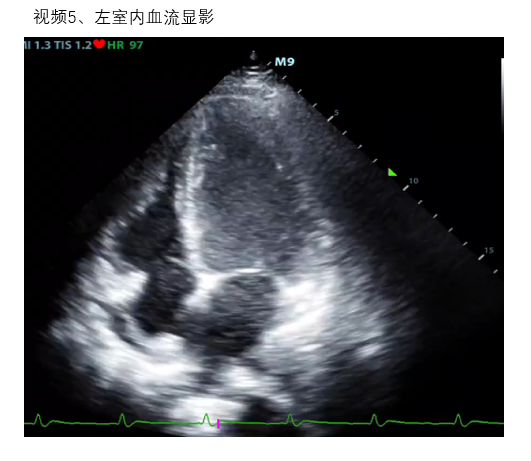

A、左心:观察左心室壁运动情况,测量左心室收缩和舒张功能,评估二尖瓣及主动脉瓣瓣膜功能。对心功能连续、及时评估可协助制定流量支持力度和决定撤机时机。通过连续性监测左室舒张末内径变化、主动脉瓣开合情况,评估左心室后负荷,制定左室减压时机与策略(图20,视频5)。当患者出现心腔内血流显影时,形成血栓风险增加,对心腔进行密切监测,调整抗凝治疗策略,预防心室内血栓形成。

图20 左心室后负荷超声监测项目

视频5 左室内血流显影

视频5-左室内血流显影